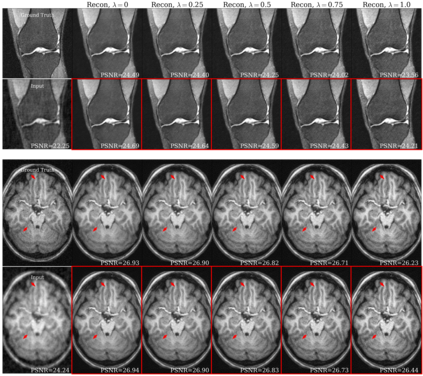

Deep learning based techniques achieve state-of-the-art results in a wide range of image reconstruction tasks like compressed sensing. These methods almost always have hyperparameters, such as the weight coefficients that balance the different terms in the optimized loss function. The typical approach is to train the model for a hyperparameter setting determined with some empirical or theoretical justification. Thus, at inference time, the model can only compute reconstructions corresponding to the pre-determined hyperparameter values. In this work, we present a hypernetwork based approach, called HyperRecon, to train reconstruction models that are agnostic to hyperparameter settings. At inference time, HyperRecon can efficiently produce diverse reconstructions, which would each correspond to different hyperparameter values. In this framework, the user is empowered to select the most useful output(s) based on their own judgement. We demonstrate our method in compressed sensing, super-resolution and denoising tasks, using two large-scale and publicly-available MRI datasets. Our code is available at https://github.com/alanqrwang/hyperrecon.